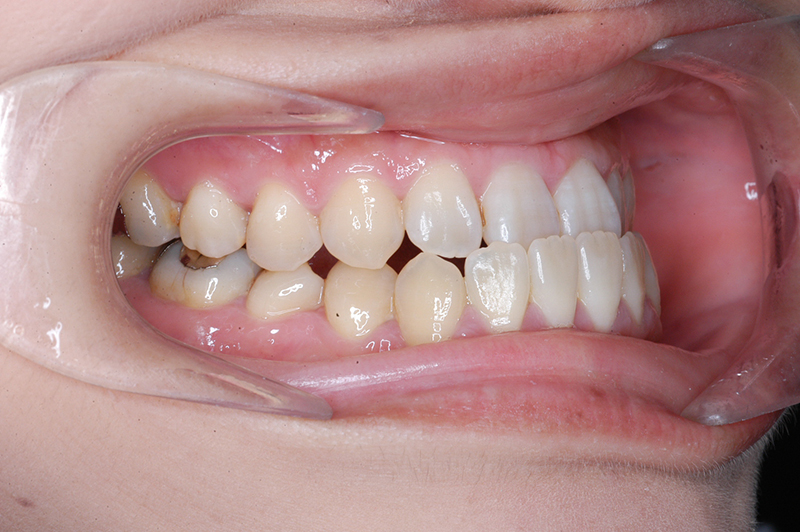

初診時

FP・IOP

口腔内所見 臼歯関係はⅢ級、下顎歯列はスピーカーブによって前歯は舌側へ倒れこみつつ挺出しておりover jet-2.5mm、over bite3.0mmと反対咬合を呈していた。